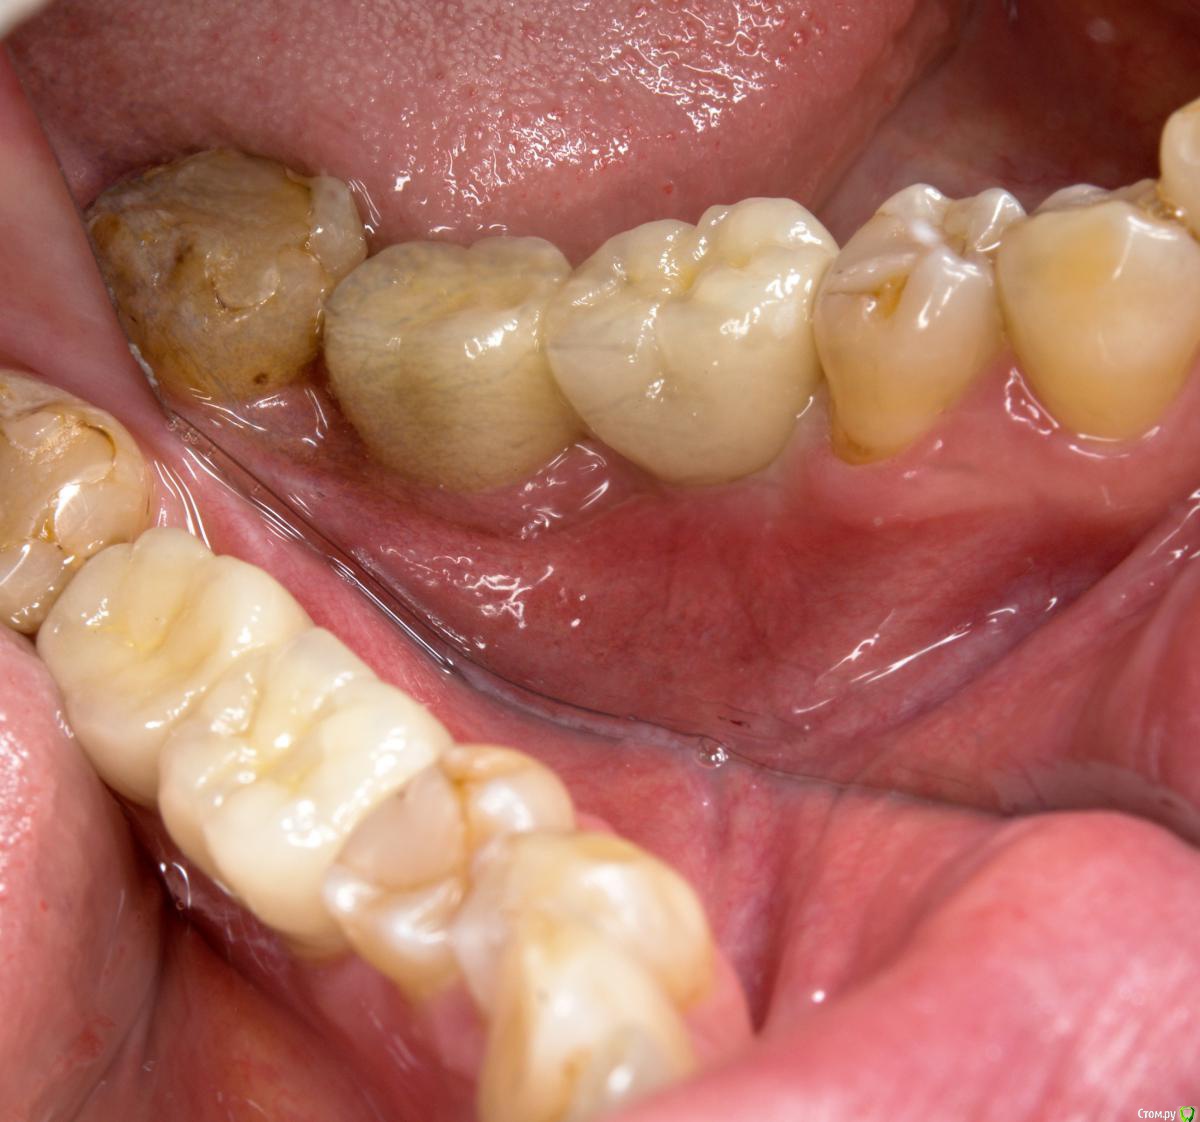

NazranDantist Опубликовано 6 сентября, 2016 Поделиться Опубликовано 6 сентября, 2016 Проведена имплантация два месяца назад, импланты SGS. Второе посещение слепок и немного модернизируем формирователи десны, третье посещение - фиксируем на готово. Дешево и сердито)). 4 Ссылка на комментарий

DmitrySH Опубликовано 6 сентября, 2016 Поделиться Опубликовано 6 сентября, 2016 А что соседей не тронули до изготовления коронок? как минимум удобнее было бы. Ссылка на комментарий

NazranDantist Опубликовано 6 сентября, 2016 Автор Поделиться Опубликовано 6 сентября, 2016 Соседние пациент не хочет пока трогать Ссылка на комментарий